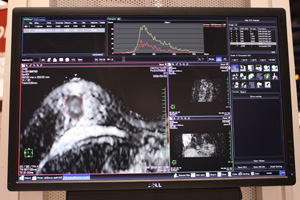

DWI解析:ADCマップのヒストグラム解析

DWI解析のもうひとつの機能として,ADCマップをヒストグラム解析する機能も紹介した(FDA未申請)。ADC値は,腫瘍学においては半定量的値として活用されており,ADC値が低いと,高い確率で悪性度が高いと言われている。AZEは,3Dワークステーションメーカーの強みを生かし,腫瘍を三次元的に抽出して,ヒストグラムを描出する方法を開発した。腫瘍の悪性度,治療の効果判定に用いるなど,読影支援ツールとして利用できる。